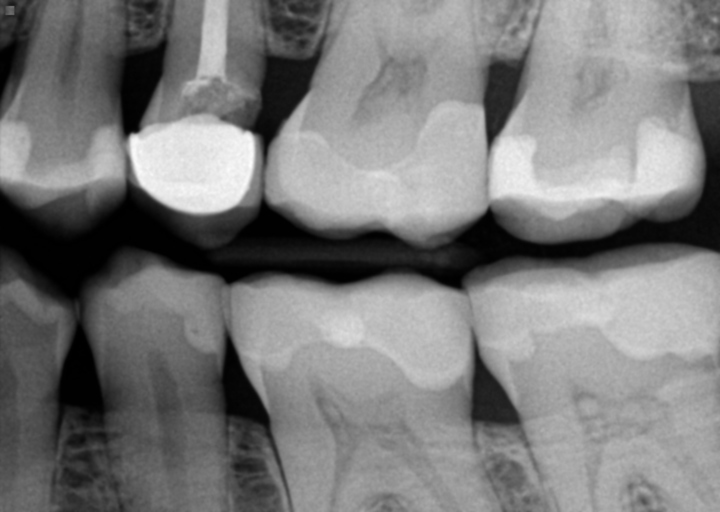

Infection at the root tip and failed root canal

I had my central incisors crowned 7 months ago. My left central incisor 2 days after became infected at the root tip. My dentist preformed a root canal and that seemed to improve the pain and infection. However, I started feeling pain near my nose and went back in to have it looked at. Indeed it was still infected. My dentist said it was chronic and she would redo the root canal. They emptied the canal and placed formocresol soaked cotton in the canal and temporarily sealed it. My first question involves the formocresol because it leaked out while they were preforming and it has essentially burnt my gum line along the entire top left pallet of my mouth. Will this harm my other teeth? My gums are red and tender like a burn from hot food all the way back to my molars. The pain near my nose has increased since two days ago when I went in and had this preformed. I was instructed to call when my symptoms (pain) has gone away completely and they will then fill my canal properly. Is this normal for the pain to worsen? I feel like the infection is getting worse since the pain has increased. I would like to know if I should see someone else or if this is routine.